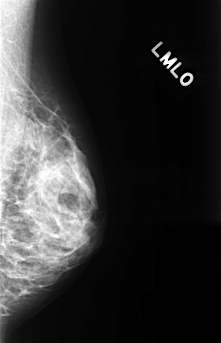

C_0327_1.LEFT_MLO

LEFT_MLO LINES 4456 PIXELS_PER_LINE 2872 BITS_PER_PIXEL 12 RESOLUTION 50 NON_OVERLAY